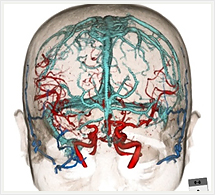

- 造影検査では、ヨード造影剤を併用することにより血管の走行など、より多くの情報をもった画像を得ることができます。

- 撮影されたCT画像をされにコンピュータで処理することにより、体軸に対する自由な輪切りの断面画像を作ることができます。

- 顔面などで表面を強調させた画像作成も可能で、まるでその人の顔を見ているような立体的でリアルな顔型をつくることもできます。

画像紹介

CTでは輪切り像の他にも立体的な画像(3D画像)を作成することもできます。そのためにはより細かくキレイな画像を撮影しなければなりません。当院では64列CTを導入しており、キレイな画像をより細かく撮影することができます。その画像を元に3D画像を作成することによって、より正確な手術のシミュレーションが可能になります。実際に手術をしたときの様子が、手術をする前に画像として見らます。外科系の手術には欠かせない技術となっておりますが、内科系でも血管内手術にも多く利用されております。

当診療放射線技術科では毎日各診療科に対して、その手術に最適な3D画像を提供しております。

以下にその3D画像を一部分紹介します。

頭部